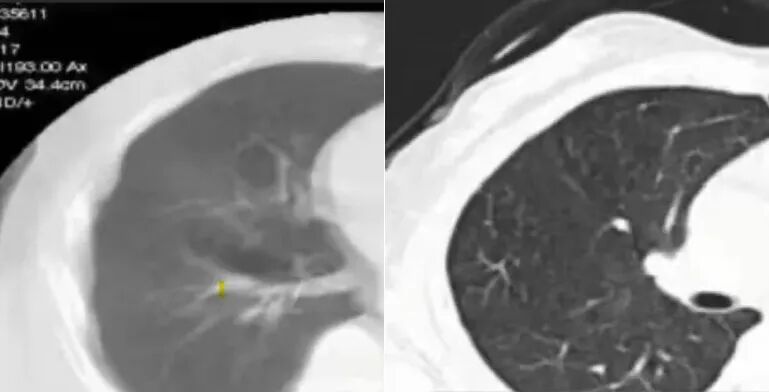

你有没有试过用手机拍跑动的小狗?画面是不是会模糊重影?咱们的肺在呼吸时也跟那小狗似的 “动个不停”,CT 扫描的时候要是肺跟着一呼一吸地动,图像就会出现 “重影”“拖尾”(这在医学上叫呼吸伪影)。

① 拉开肺组织,让病灶 “无处藏”

深吸气的时候,肺泡膨胀、肺间隙被 “撑开”,就像把皱巴巴关闭的窗帘彻底拉开 —— 哪怕是 5mm 的微小结节、早期炎症,也会在 “全景视野” 下显露出真面目。用影像科医生的话说:“这就是病灶的‘曝光时刻’,再小的问题也藏不住。”